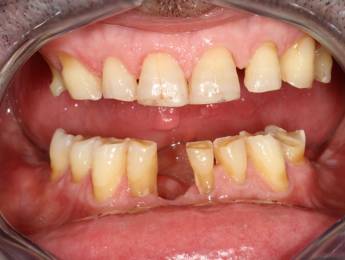

6. Eset

Nagymértékű fogkopás, erózió, csikorgatás a teljes rágóapparátust túlterhelve okoz reménytelennek tűnő helyzeteket.

Ebben az esetben implantátumok , koronák és hidak segítségével változtattunk a páciens fogainak érintkezésén. 6 hónapig ideiglenes hidakkal teszteltük a megváltoztatott harapási pozíciót. Ezután készültek el a végleges fix pótlások.